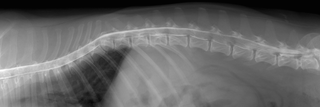

環軸不安定症 AAI

AAIとはヨークシャーテリア、チワワなどの超小型犬に発症する第一頚椎と、第二頚椎の不安定性による頸髄の障害です。通常、頚部痛、四肢不全麻痺などの症状がでます。

悪化すれば呼吸停止により突然死することもあります。